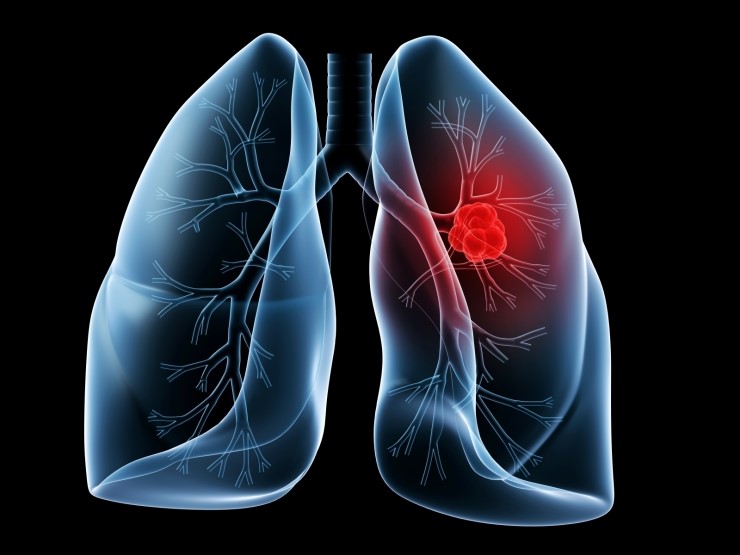

폐암의 초기증상 중에 흉통이 있습니다. 폐암 환자의 약 1/3이 흉통을 호소합니다. 흉통의 원인은 폐 가장자리에 종양이 형성되어 암세포를 생성하고 흉벽과 흉막에 침착되어 통증을 유발하는 것입니다.

흉통의 원인은 여러 가지가 있을 수 있지만, 오늘날 우리가 다루고 있는 폐암으로 인한 흉통은 경미한 통증보다는 지속적인 따끔거림과 둔한 통증을 동반한다는 점에 유의하시기 바랍니다. 또한 암은 흉막이나 흉벽 대신 갈비뼈로 퍼져 통증을 유발할 수 있습니다. 종양은 주변 조직 세포를 자극할 수 있으므로 계속해서 통증을 유발하는 경우 의사의 진찰을 받는 것이 좋습니다.